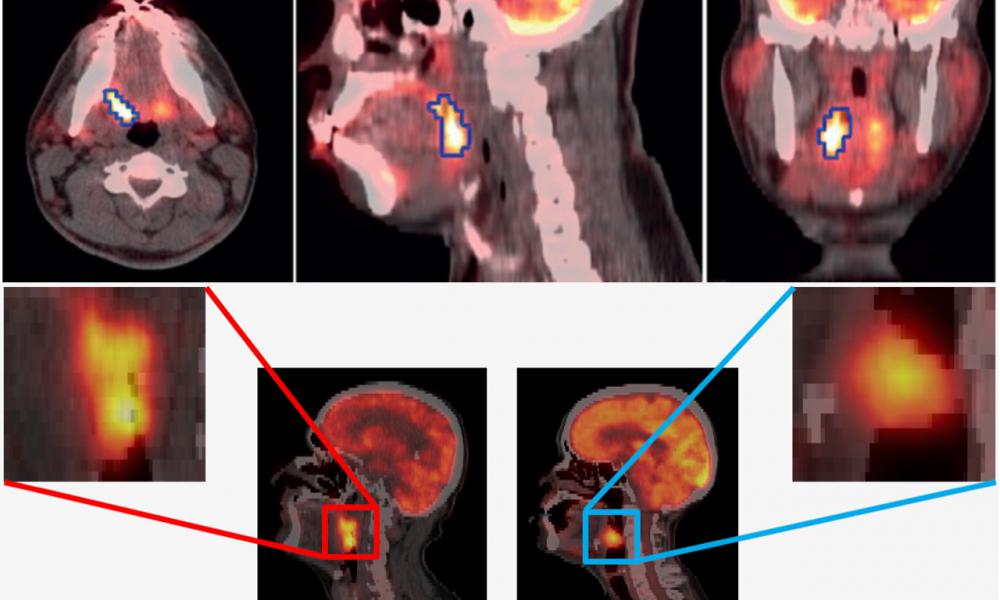

We pursue interdisciplinary research towards enhanced quantitative nuclear medicine (radiomolecular) imaging (PET & SPECT). Coupled with our provincial functional imaging and therapy program, we emphasize partnerships with other collaborators, clinical sites and industry, aiming to translate our image generation and analysis methods (including artificial intelligence) to state-of-the-art patient care and to impact quality of life. Our efforts include:

- Quantitative PET imaging methods for enhanced diagnosis, prognosis and treatment response assessment of cancer patients (e.g. prostate cancer, lymphoma, lung cancer, …)

- AI and Radiomics methods as applied to PET and SPECT imaging of cancer